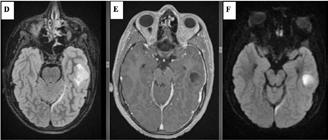

Patternuri de infiltrare a măduvei osoase în MM decelate prin IRM (figura )

Leziunile MM sunt prezente predominant în scheletul axial și anume vertebre (66%), pelvisul osos (30%) și într-o măsură mai mică la nivelul scheletului extra-axial (coaste, schelet apendicular) [20] În literatură sunt descrise cinci tipuri de infiltrare a măduvei osoase în mielomul multiplu: măduvă cu aspect normal, infiltrare focală a măduvei osoase, infiltrare difuză, infiltrare de tip “sare și piper” și infiltrare combinată focală și difuză [21, 22]; Există o multitudine de studii apărute în literatură care corelează aceste tipuri de infiltrare medulară cu modificările vizualizate la examenele morfo-patologice [23, 24]. În majoritatea cazurilor de MM (28%) se observă un aspect normal al măduvei osoase, cu hipersemnal T1 omogen al acesteia; în cazul infiltrarii, focale se observă diverse leziuni focale T1 hipointense, care pot apărea oriunde la nivelul scheletului; în cazul infiltrării difuze, se observă hiposemnal T1 difuz la nivelul intregii măduve osoase, uneori în caz de infiltrare severă, semnalul fiind chiar mai redus decât cel al discului intervertebral. În doar 3% din cazuri se observă un model de tip „sare și piper” și în 11% din cazuri se poate observa un model mixt de infiltrare nodulară și difuză [22, 25]

Tipuri de afectare medulară în mielomul multiplu: aspect normal imagistic(a), infiltrare focală(b), infiltrare difuză(c) infiltrare de tip ‘sare și piper’, infiltrare mixtă de tip focal și difuz(d). Departamentul de Radiologie al Spitalului Clinic Municipal de Urgență - Timișoara/RO